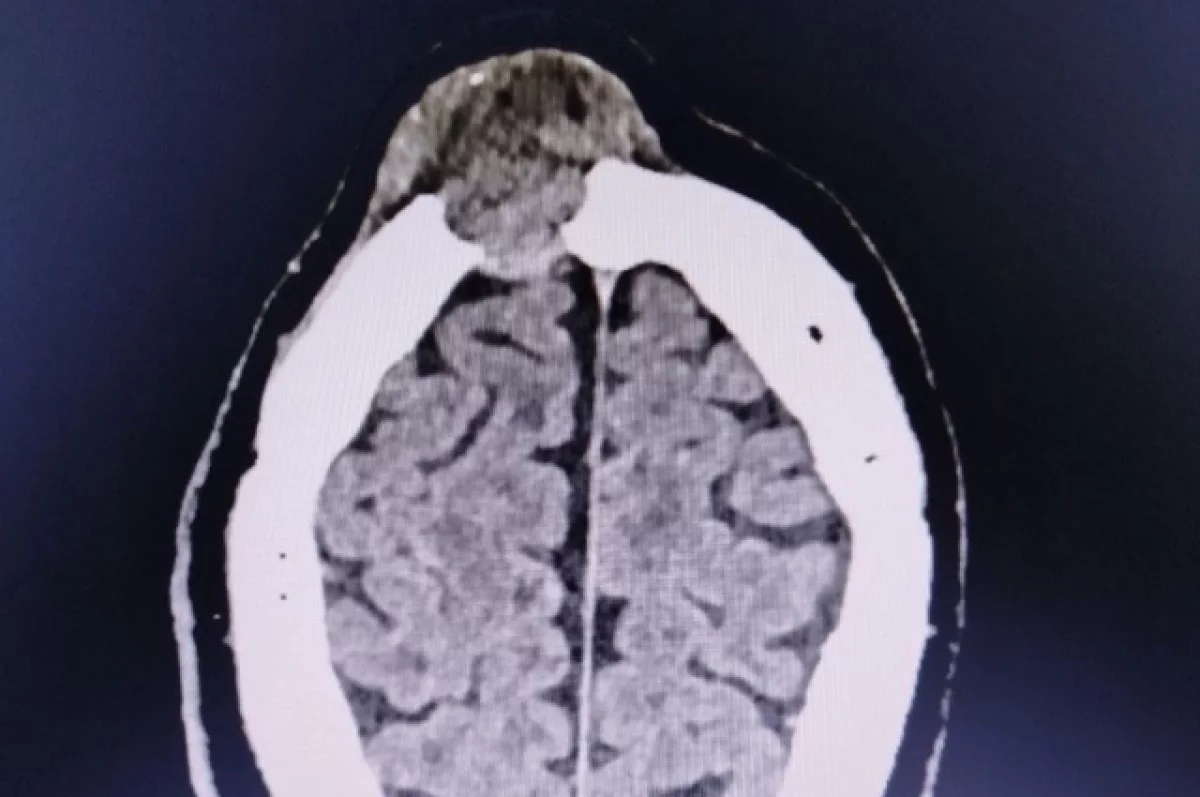

«Компьютерная томография показала опухоль, которая уже разрушала лобную кость. Пациента госпитализировали в нейрохирургическое отделение», — рассказали в пресс-службе.

Врачи также установили, что один край новообразования располагался над самой крупной веной мозга, а другой разрушал стенки лобных пазух, что серьёзно осложняло ситуацию. Выполнять хирургическое вмешательство взялись нейрохирурги Владимир Пашкин Владимир и Ольга Мурашова. В ходе операции они аккуратно вырезали опухоль и очистили поражённые лобные пазухи, а также восстановили целостность кости лба с помощью титановой пластины.